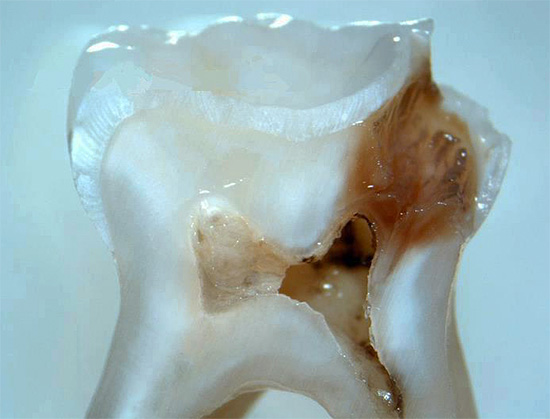

Foto de um dente com uma cárie profunda que atinge a câmara pulpar:

Geralmente, no dente, há uma cavidade profunda e cárie com dentina infectada amolecida, que freqüentemente se comunica com a câmara pulpar.Para esclarecer a presença dessa mensagem, o dentista usa uma sonda - um instrumento de metal curvo e afiado no final da sondagem.

Durante esse procedimento, fica claro se há uma mensagem no fundo da cavidade com a polpa do dente. Se houver uma mensagem, depois de sentir a polpa, muitas vezes começa a sangrar dolorosamente.

O diagnóstico por raio-X também é importante. Na pulpite fibrosa crônica, uma cavidade profunda de cárie, que quase sempre se comunica com a câmara pulpar, geralmente pode ser observada na radiografia de um dente doente. Às vezes, uma ligeira expansão do espaço periodontal (o espaço entre a raiz e o osso dos alvéolos nos quais está fixado) é fixada.